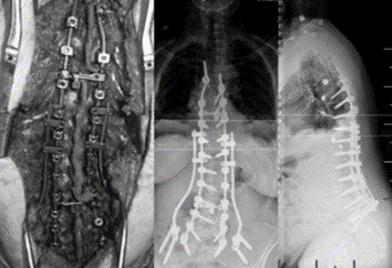

(4)Topping-Off 技术

Topping-off技术又称为融合区+上位邻近节段动态稳定技术

即从融合节段向活动节段过度的手术,旨在融合节段和活动节段之间形成缓冲区,降低邻近节段应力集中

图34-35 据文献报道,可应用一种环形和夹层胶带的技术,以重新创建一个有机后张力带UIV和UIV+1之间将上下棘突绑扎后,增强交界区后方张力带结构强度

(5)半坚强固定

据文献报道,半坚强固定可使得近端建立从僵硬固定区到非融合区有一个平缓的过渡,避免在上固定椎区域有一个应力的集中,可以避免交界性后凸的发生。

图36 多棒固定向两棒固定的过渡

图37 半坚强固定